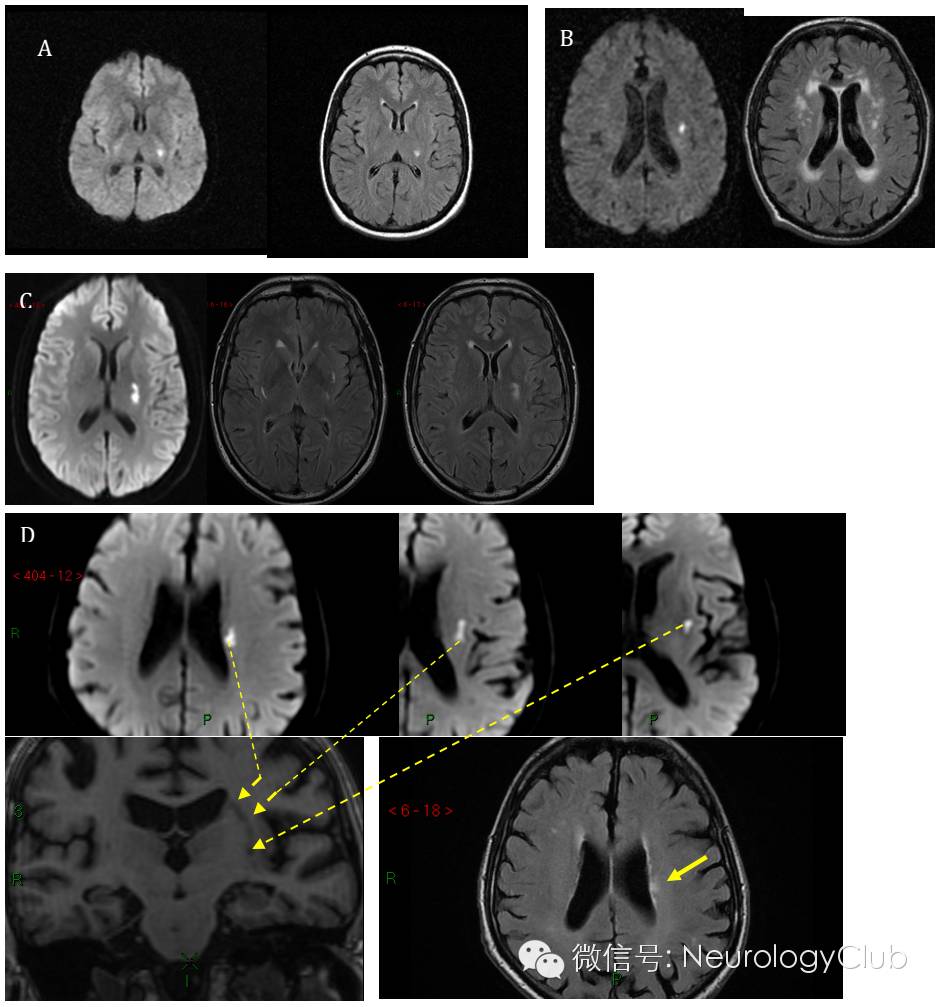

(DWI和FLAIR上不同部位形状的急性小梗死。A:内囊后肢小的卵圆形梗死;B:半卵圆中心小圆形梗死,伴白质高信号;C:内囊后肢稍大的卵圆形梗死,可见其他腔隙;D:外囊至半卵圆中心的管状梗死)